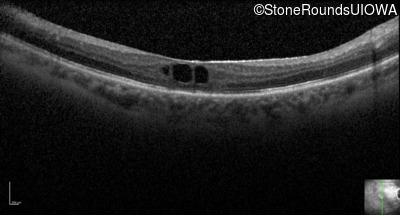

Optical Coherence Tomography - Left - 20/160

Exemplar / OCT Stack